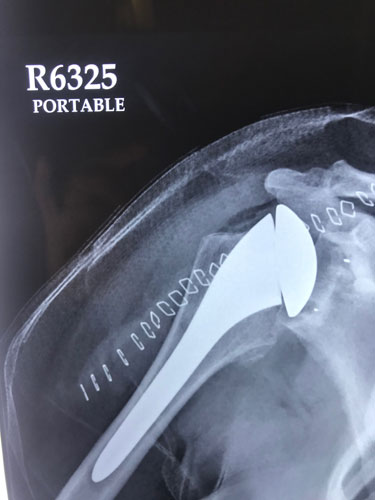

Post Shoulder Replacement Surgery X-Ray for Arthritis